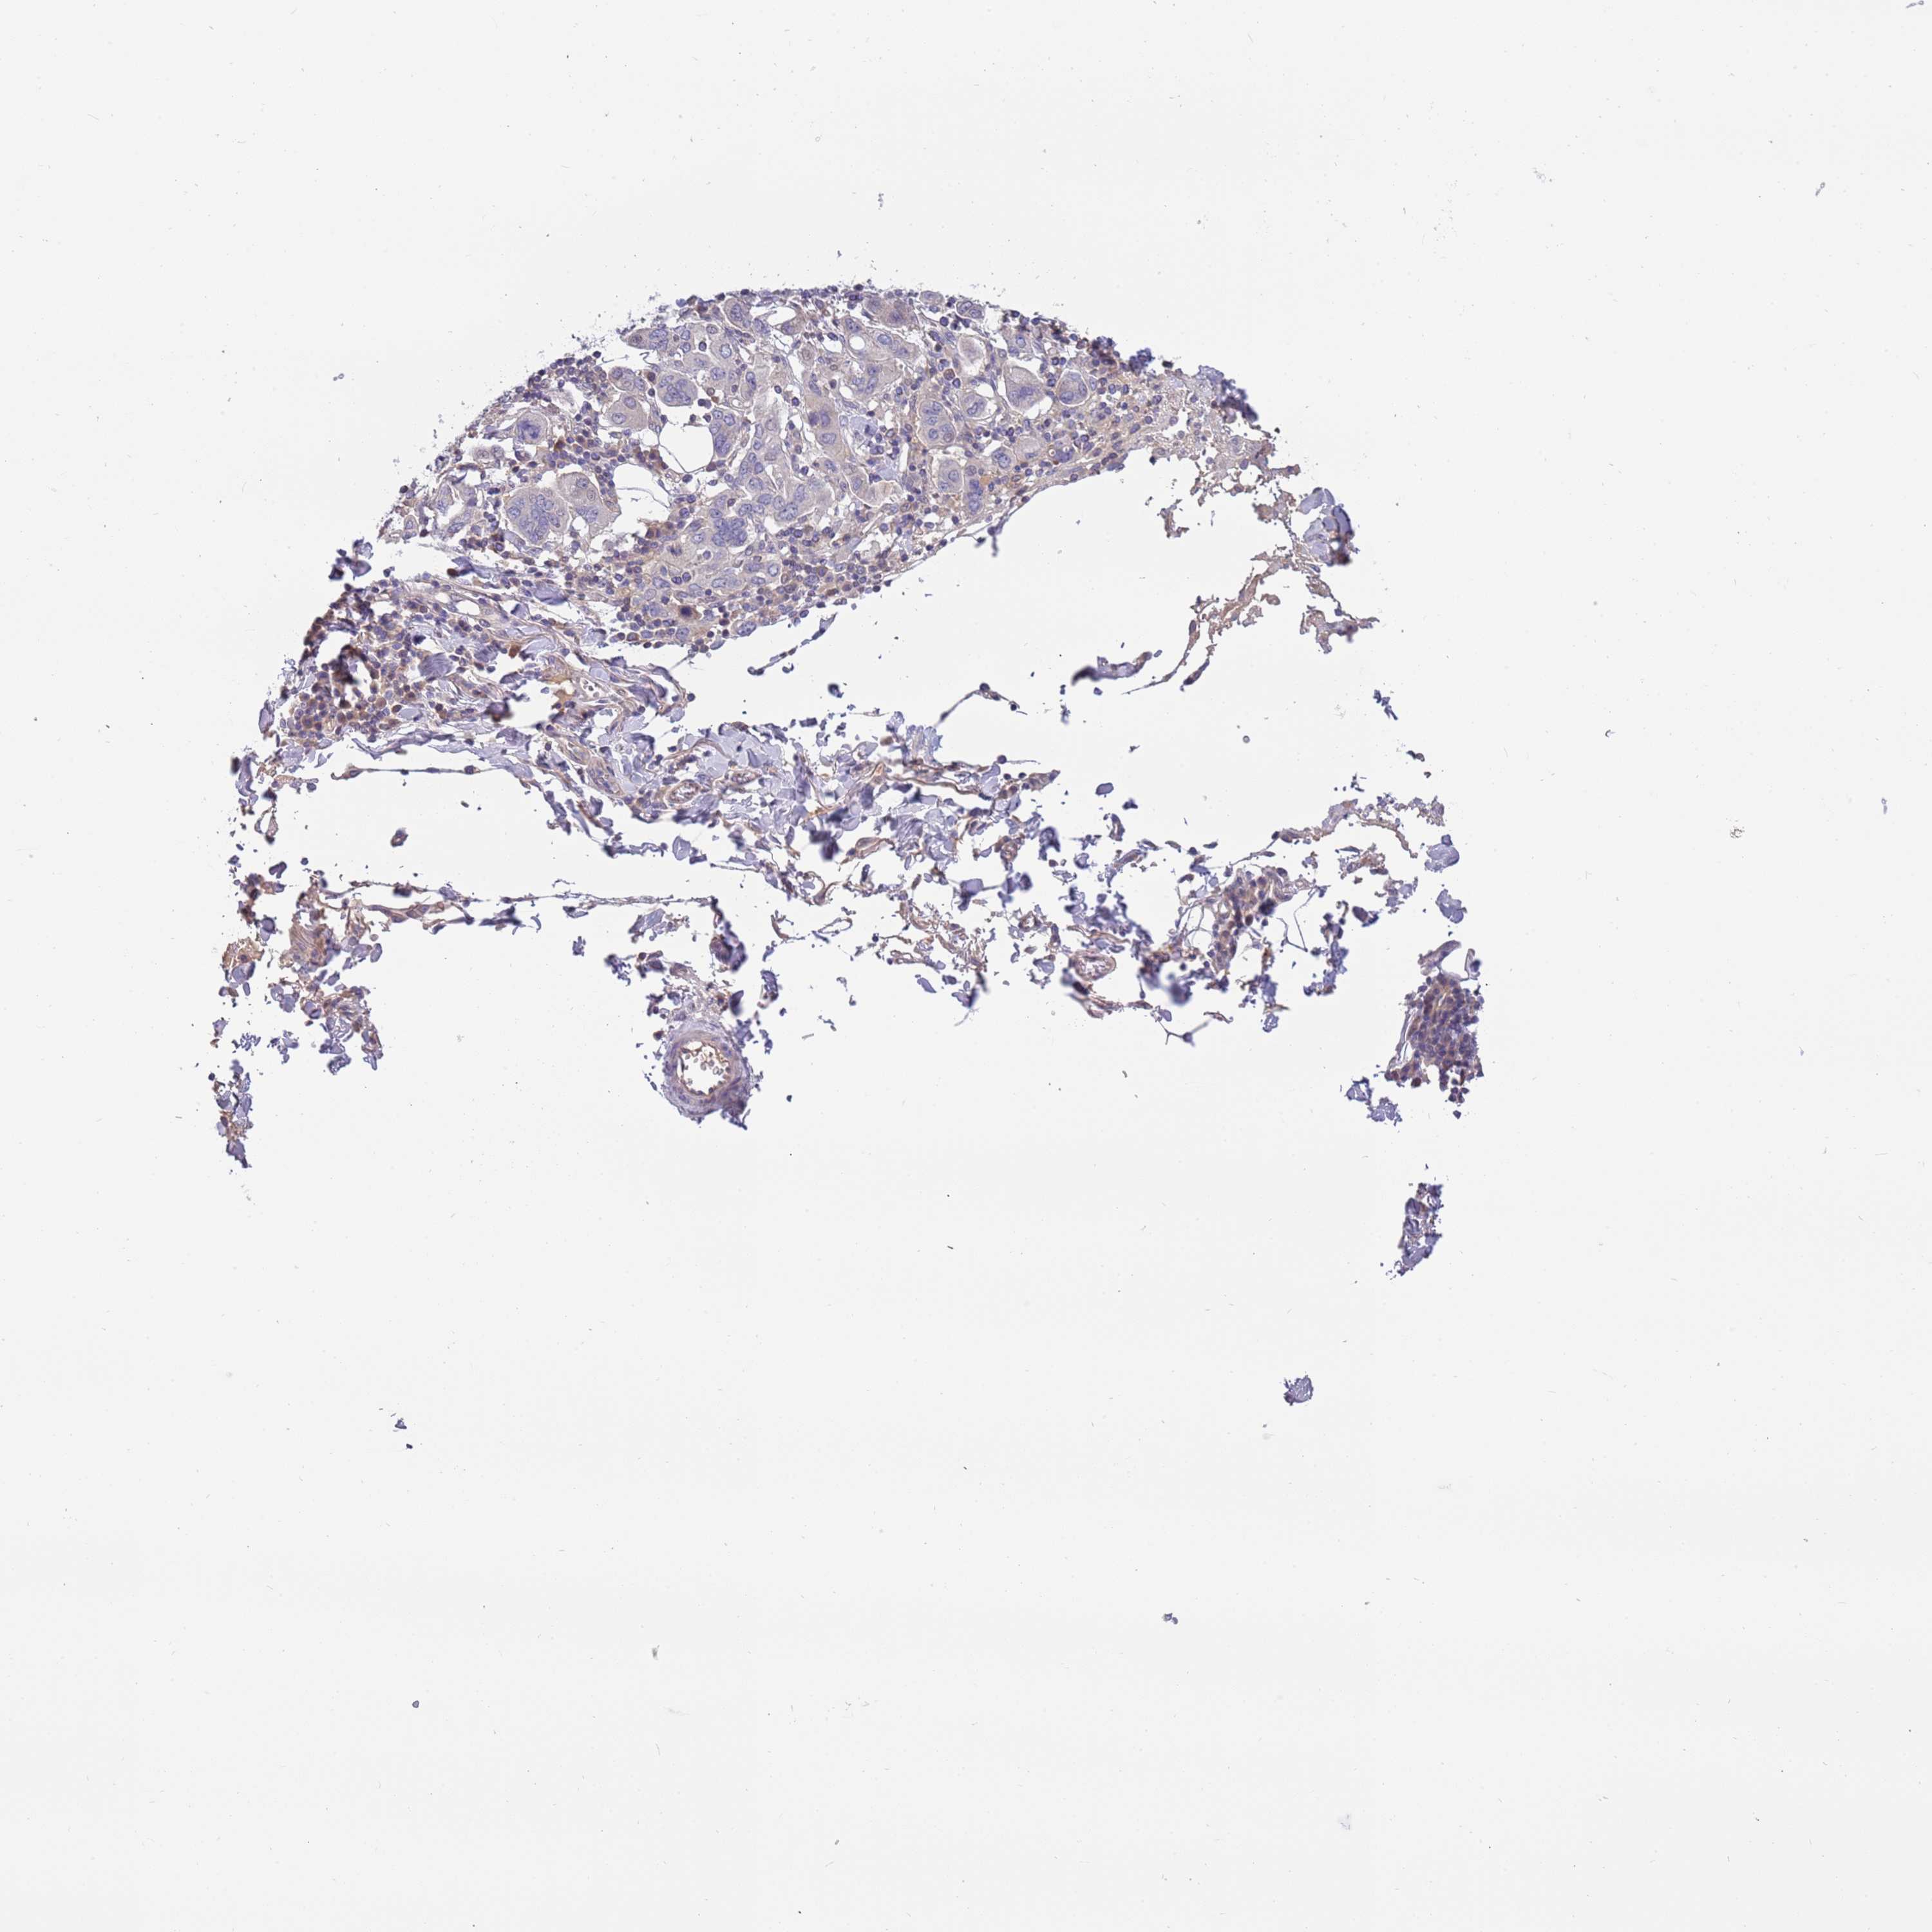

STOMACH CANCER - Protein expressioni

A mouse-over function shows sample information and annotation data. Click on an image to view it in a full screen mode. Samples can be filtered based on level of antibody staining by selecting one or several of the following categories: high, medium, low and not detected. The assay and annotation is described here.

Antibody stainingi

Antibody staining in the annotated cell types in the current human tissue is reported as not detected, low, medium, or high, based on conventional immunohistochemistry profiling in selected tissues. This score is based on the combination of the staining intensity and fraction of stained cells.

Each image is clickable and will lead to virtual microscopy that enables deeper exploration of all samples and also displays staining intensity scores, fraction scores and subcellular localization as well as patient and tissue information for each sample.

Antibody HPA040703

Antibody HPA047801

Staining

High

Medium

Low

Not detected

Intensity

Strong

Moderate

Weak

Negative

Quantity

>75%

75%-25%

<25%

None

Location

Nuclear

Cytoplasmic/membranous

Cytoplasmic/membranous,nuclear

Adenocarcinoma, NOS

Adenocarcinoma, High grade